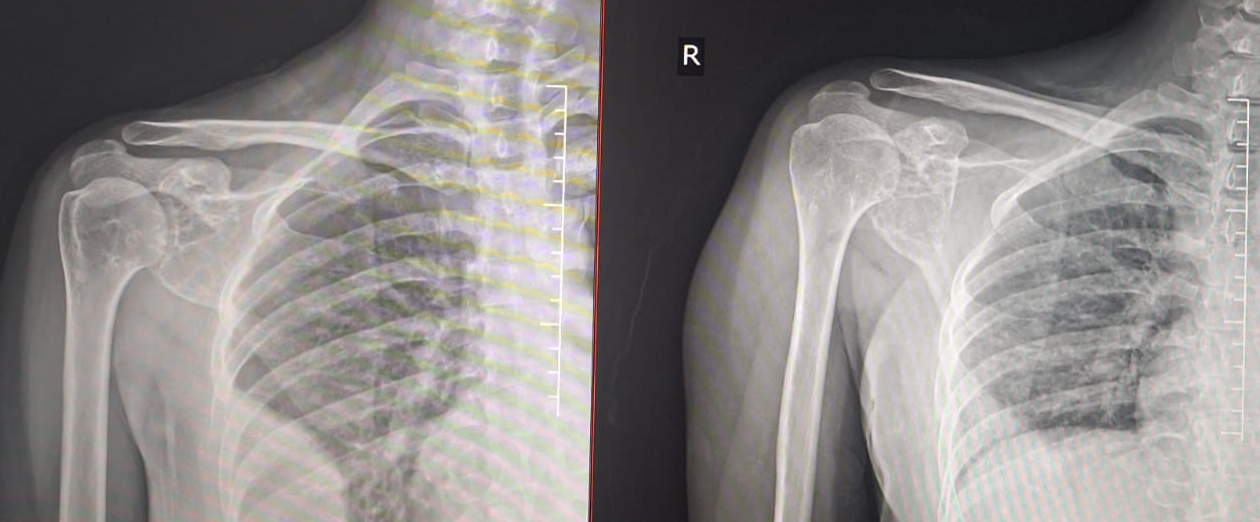

Subsequent follow-up imaging from 2023 to 2025 showed continued multifocal progression. A rapidly enlarging lytic lesion was identified in the right glenoid bone found to regress in follow-up x-ray (Fig 9). An additional lytic foci appeared in the right iliac bone in latest follow-up of 2025 ( Fig 10) when she presented with complaints of mild pain from right groin. Despite the aggressive radiologic appearance, repeat biopsy demonstrated benign hemangiomatous tissue without features of malignancy, hence we did not plan for any intervention.

• Rapidly progressive right glenoid bone lesion regressing in follow-up (Fig 9).